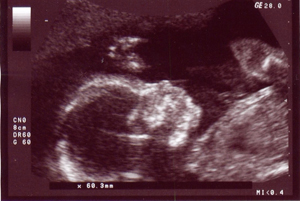

Отмечается, что Россия занимает плачевное первое место в мире по числу совершаемых абортов. По данным Росстата, у нас ежегодно проводится 1,3 млн. таких операций, что практически равно числу рождающихся за это время детей – 1,8 миллиона. Согласно статистике, каждый час в стране проводится 300 хирургических вмешательств по прерыванию беременности.